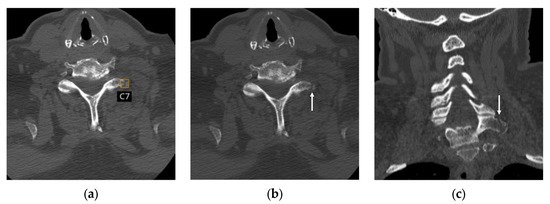

Multicenter, Multinational, and Multivendor Validation of an Artificial Intelligence Application for Acute Cervical Spine Fracture Detection on CT

by Jinkyeong Sung, Peter D. Chang, Angela Ayobi, Martina Cotena, Mar Roca-Sogorb, Jinhee Jang, Daniel S. Chow and Yasmina Chaibi

Diagnostics 2026, 16(2), 194; https://doi.org/10.3390/diagnostics16020194 - 7 Jan 2026

Background/Objectives: While previous studies have evaluated AI algorithms for cervical spine fracture (CSFx) detection on CT, many have lacked validation on diverse, multinational datasets or have focused primarily on overall case-level classification This study aimed to evaluate the performance of an AI application [...] Read more.

Background/Objectives: While previous studies have evaluated AI algorithms for cervical spine fracture (CSFx) detection on CT, many have lacked validation on diverse, multinational datasets or have focused primarily on overall case-level classification This study aimed to evaluate the performance of an AI application for acute CSFx detection in case-level classification, fracture localization, and spinal level labeling on multicenter, multinational, and multivendor CT data. Methods: Non-enhanced CTs were retrospectively collected from a U.S. teleradiology company, a French teleradiology company, and a U.S. university hospital. Four radiologists independently labeled the presence and location (including the spinal level) of acute CSFx to establish the reference standard. Per-case diagnostic performance, per-bounding box positive predictive value (PPV) for localization, and overall agreement of cervical vertebral level labeling of the AI were assessed. Results: A total of 155 patients (60.6 years ± 21.2 years, 104 men) with acute CSFx and 173 patients (51.9 years ± 22.7 years, 91 men) without acute CSFx were evaluated. Data were acquired using scanners from five manufacturers. For acute CSFx diagnosis, the AI achieved a per-case sensitivity of 90.3%, a specificity of 91.9%, an accuracy of 91.2%, an area under the receiver operating characteristic curve (AUC) of 0.91, and Matthews correlation coefficient of 0.82. Among 192 bounding boxes representing acute CSFx generated for 154 positive cases by the AI, 162 were true positives (per-bounding box PPV, 84.4%). Of the 186 bounding boxes for which the AI displayed cervical spinal level, 181 were labeled correctly (overall agreement, 97.3%). Conclusions: The AI application for detecting acute CSFx demonstrated high diagnostic performance on multicenter, multinational, and multivendor data, with high performance in fracture localization and spinal level labeling. Full article

(This article belongs to the Special Issue Contemporary Spine Diagnostics and Management)

Show Figures

Figure 1